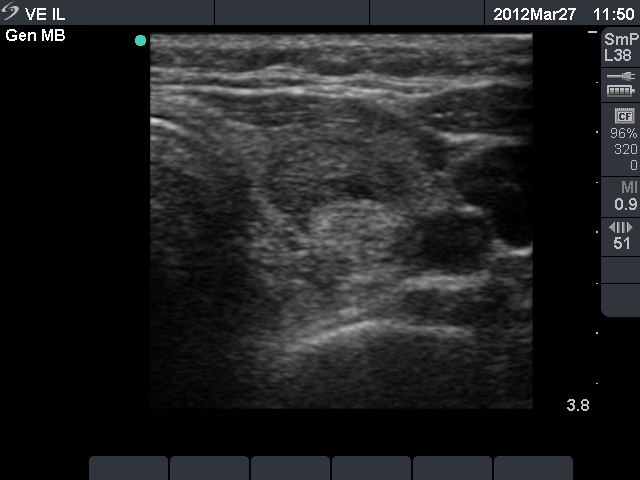

Ultrasonography: the thyroids were echonormal and contained multiple small hypoechogenic lesions. There was a mixed moderately hypoechogenic-echonormal nodule in the left lobe. The nodule exhibited a halo sign and peri- and intranodular blood flow.